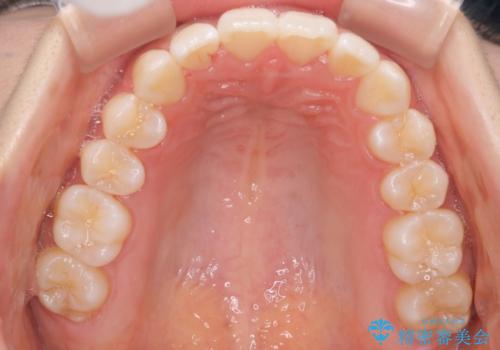

[ ディープバイト ] 深い噛み合わせの改善 マウスピース矯正

![[ ディープバイト ] 深い噛み合わせの改善 マウスピース矯正の症例 治療前](https://seimitsushinbi.jp/wp/wp-content/uploads/2022/03/dc9c092565b160bca6dd53d63f6aeffb-500x350.jpg?v=1646893459)

![[ ディープバイト ] 深い噛み合わせの改善 マウスピース矯正の症例 治療後](https://seimitsushinbi.jp/wp/wp-content/uploads/2022/03/5f1b12b750c3b8c04cdc49e53bc8f89d-500x350.jpg?v=1646893434)